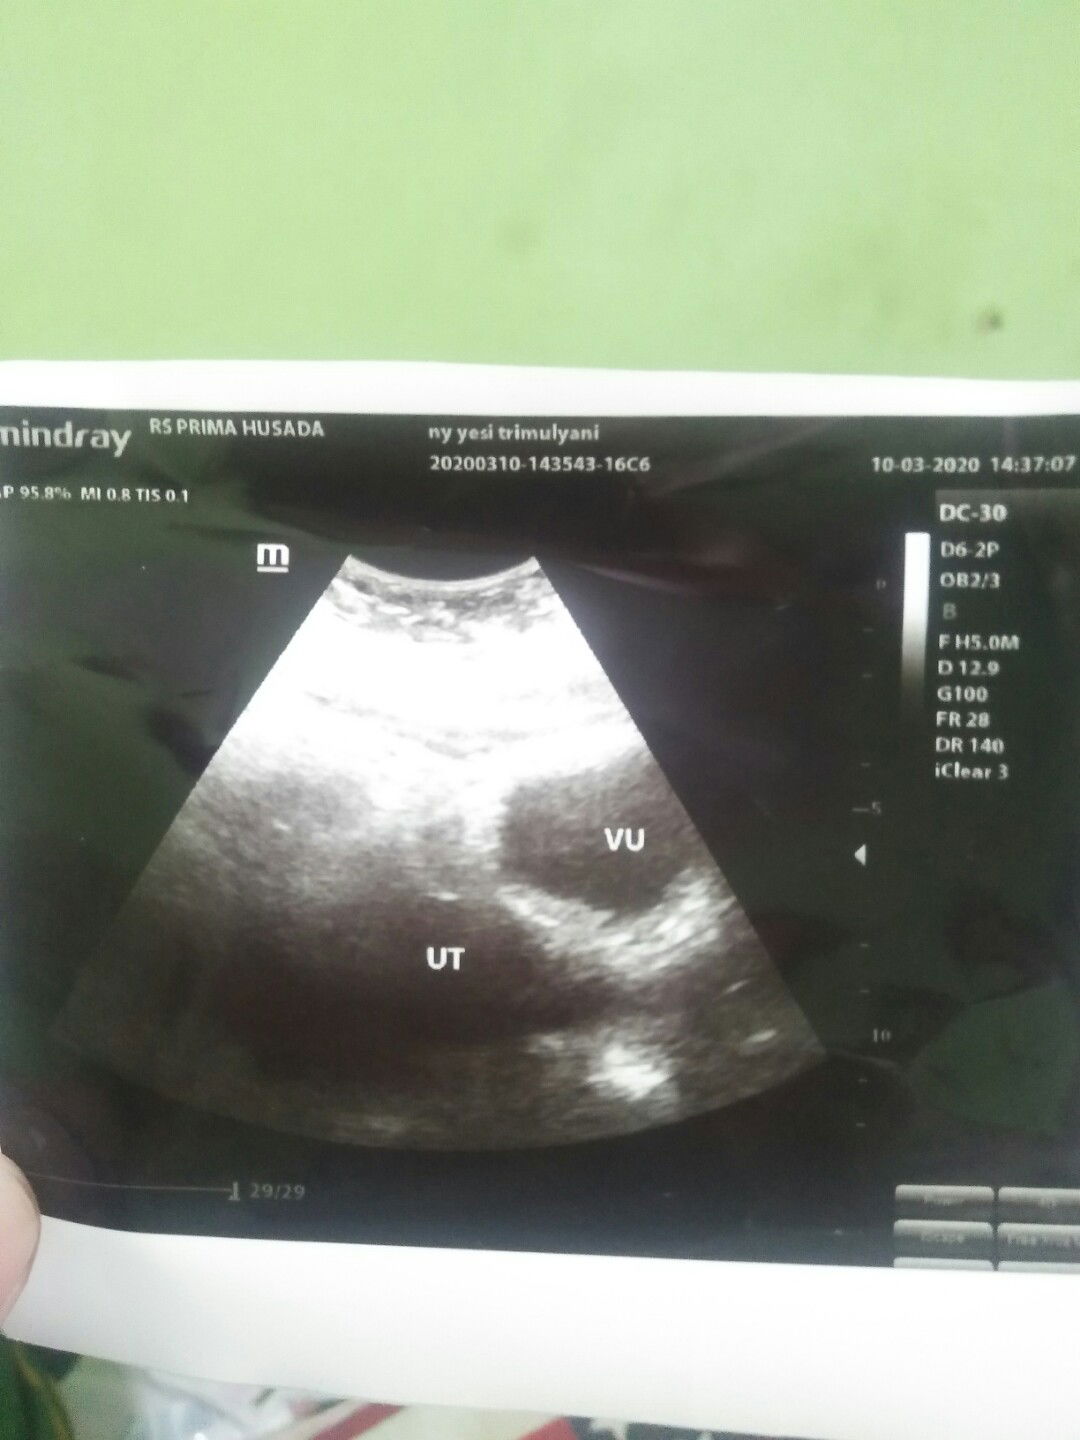

USG

Bunda saya mau bertanya hptp saya 7 februari 2020 , dan saya sudah telat 7 hari, waktu saya tespack alhamdulillah garis 2. Tapi pada saat saya kontrol untuk usg, dokter bilang masih belum terlihat semuanya (kantong rahim dan janin). Apakah begitu bun??

Klu aku dlu dbilangin bun..emng iya,ada yg Msih pnebalan rahim.sya hpht 19januari..priksa pas telat d 10hari tgl 27 feb..trhtung dri hpht brrti 5w6d tp msih penebalan..dikasih vit suruh balik lg 2mnggu..